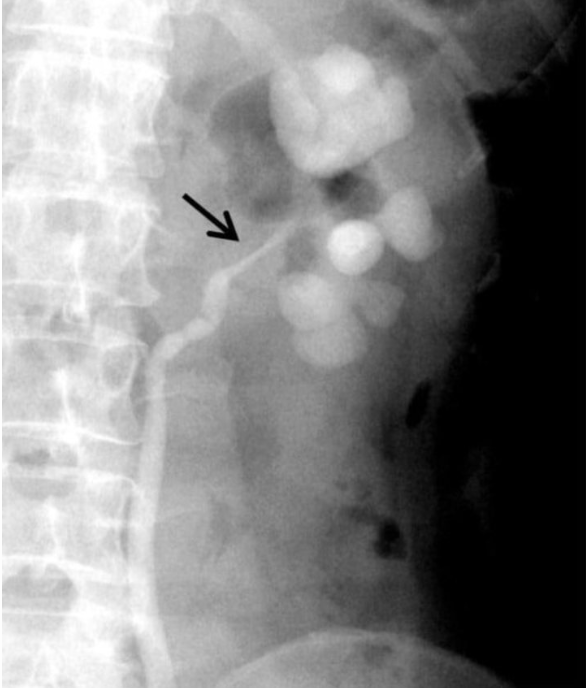

The given Retrograde ureterogram showing dilated clubbed calyces with stricture of the left ureteropelvic junction is suggestive of _____